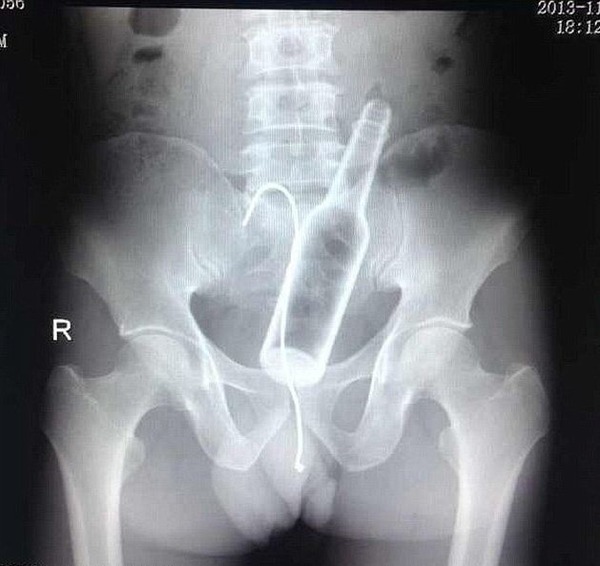

お尻は日本でもたまーに救急に来るで

肛門 異物

肛門に異物はよくあるらしい。やり過ぎると地主になってしまうので程ほどにね。

直腸内で破砕せざるを得なかった巨大直腸異物の1例

↑こんな感じで学会で報告されるそうだな…

そのままググれば文章出てくるわ

尻に異物が入る時はだいたい「転んだ拍子に」って言うけど医療関係者はそんな与太話は誰も信じてないだろうね。